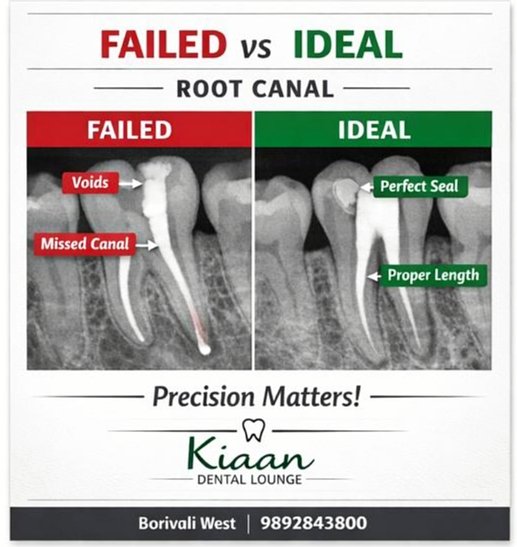

Root Canal Treatment

Our clinic offers safe and effective root canal treatment to save infected or damaged teeth. Using advanced techniques and gentle care, we remove infection, relieve pain, and restore your tooth’s natural function.